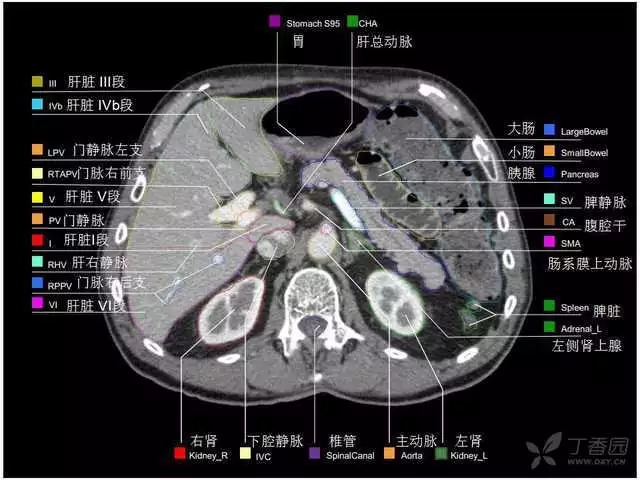

腹部肝脏高清CT断层的图谱

全腹部高清CT图谱,淋巴结彩色图谱,血管解剖图谱大汇总!

超声肝脏分叶及分段

肝脏分段和基本解剖学标志